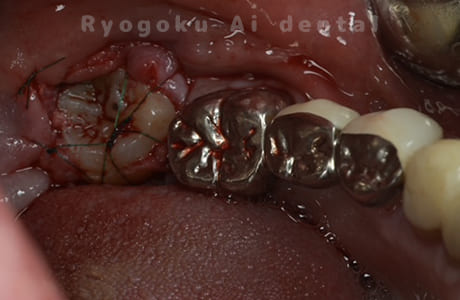

他院で右下の根の治療を行い、セラミックを被せる説明をされていたが、根の治療が終わらないため転院された患者さんです。隣の親知らずの抜歯の必要性と、根の治療を行なっている歯牙の予後が悪いため、移植治療を提案し、右下の親知らずの抜歯と同時に、右下の奥歯(7番)への移植治療を行いました。被せ物を行う必要もなく、順調に経過してます。